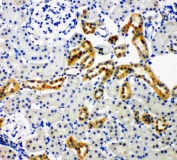

IHC-P: NOX4 antibody testing of rat kidney tissue. Required HIER: Boil the paraffin sections in 10mM citrate buffer, pH6, for 20 min.